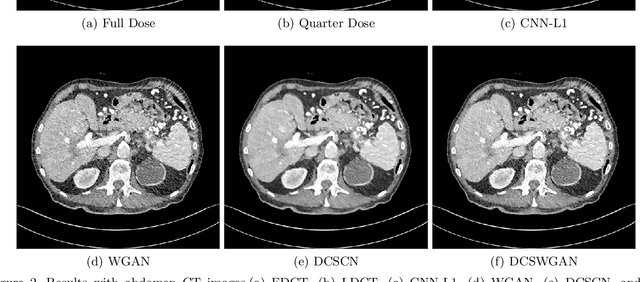

Abstract:A major challenge in computed tomography (CT) is how to minimize patient radiation exposure without compromising image quality and diagnostic performance. The use of deep convolutional (Conv) neural networks for noise reduction in Low-Dose CT (LDCT) images has recently shown a great potential in this important application. In this paper, we present a highly efficient and effective neural network model for LDCT image noise reduction. Specifically, to capture local anatomical features we integrate Deep Convolutional Neural Networks (CNNs) and Skip connection layers for feature extraction. Also, we introduce parallelized $1\times 1$ CNN, called Network in Network, to lower the dimensionality of the output from the previous layer, achieving faster computational speed at less feature loss. To optimize the performance of the network, we adopt a Wasserstein generative adversarial network (WGAN) framework. Quantitative and qualitative comparisons demonstrate that our proposed network model can produce images with lower noise and more structural details than state-of-the-art noise-reduction methods.